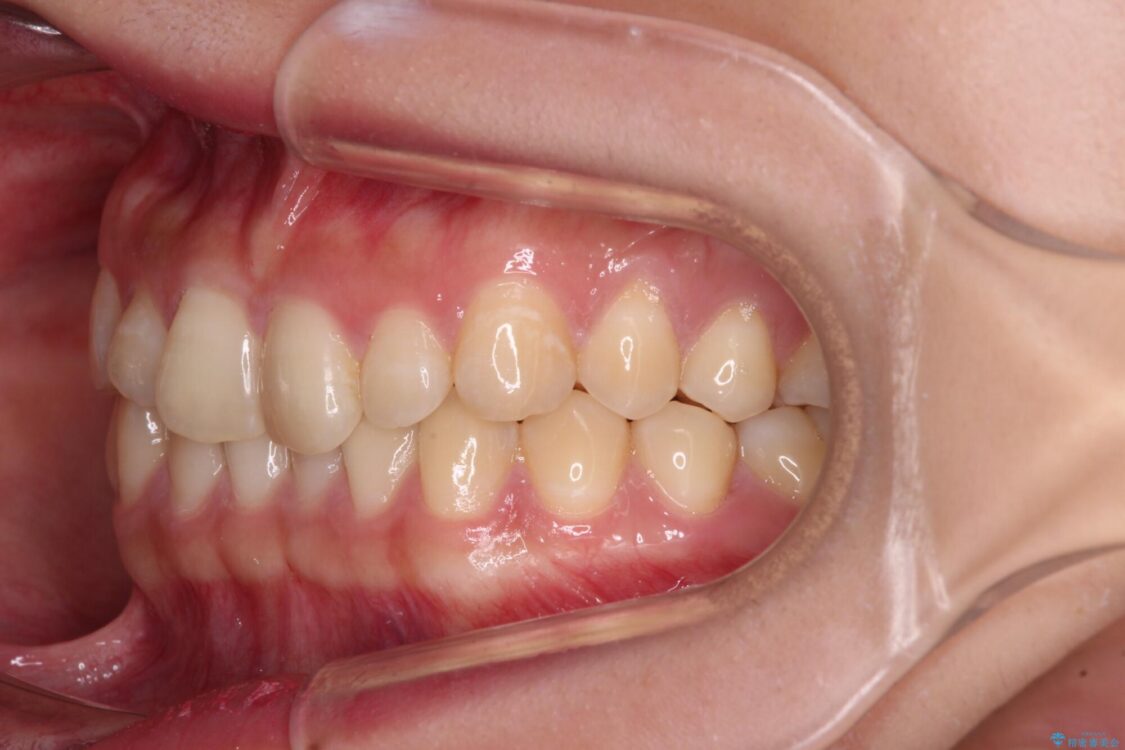

根管治療を行ったままの奥歯と、矯正治療の後戻りを気にして来院された患者様です。

矯正治療の後戻りは軽微であったため、インビザラインの簡易パッケージであるインビザライン・ライトを用いて歯列を整えることとしました。

治療前

• 治療途中の奥歯と矯正治療の後戻り インビザライン・ライトによる矯正治療 治療前画像